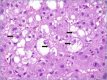

Non-alcoholic fatty liver disease (NAFLD) encompasses a spectrum of different conditions which are characterized by hepatic steatosis in the absence of secondary causes. It is currently the most common chronic liver disease worldwide, and its estimated prevalence is about 1.5-6.5%. The only histological finding of steatosis ("simple" steatosis) represents the uncomplicated form of NAFLD, while non-alcoholic steatohepatitis (NASH) is its inflammatory subtype associated with disease progression to cirrhosis and hepatocellular carcinoma (HCC), and represents the major indication for liver transplantation. NASH is still a diagnostic and therapeutic challenge for clinicians and liver biopsy is currently the only accepted method to reliably distinguish NASH from "simple" steatosis. From the histological perspectives, NAFLD and NASH continue to be an area of active interest for pathologists, with a specific focus on better methods of evaluation, morphologic clues to pathogenesis, and predictors of fibrosis progression. This review focuses on histopathology of NAFLD in adults, with the aim to provide a practical diagnostic approach useful in the clinical routine.